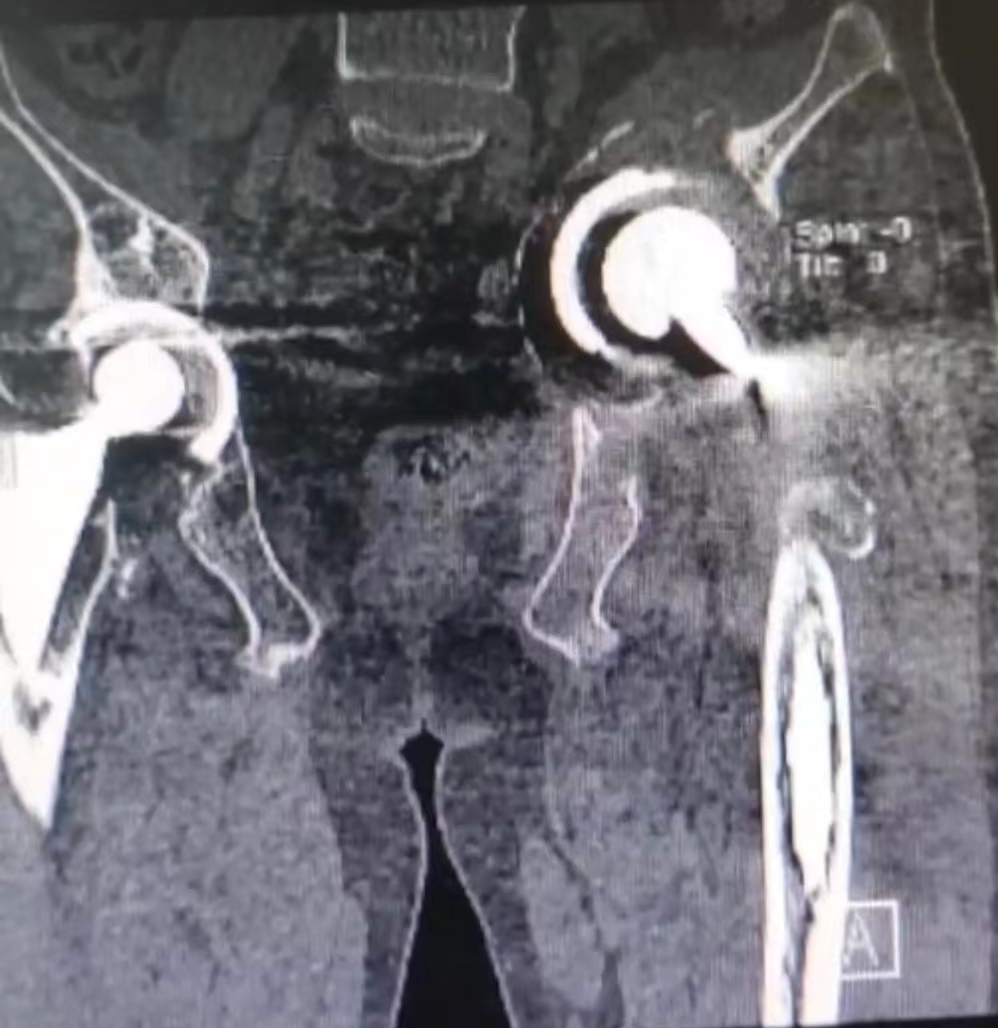

术前左侧假体松动脱位